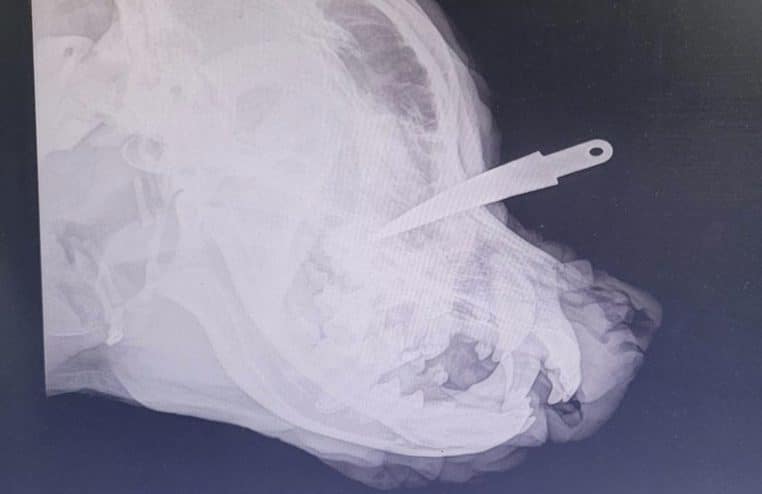

Dans le département de l’Eure (27), un chien a été retrouvé dans un état horrifiant sur le bord d’une route ce vendredi 23 juin 2023. Échappant à la vigilance de ses maîtres, le Rottweiler aurait subi d’affreuses tortures. Traîné à l’arrière d’une voiture, une lame de 7 cm a été enfoncée entre ses yeux.

Montrant des traces importantes de brûlures, l’animal aurait « été traîné par sa longe derrière une voiture avec certitude » d’après la vétérinaire et les gendarmes qui l’ont pris en charge. Poignardé entre les deux yeux, Tyron a ainsi été victime d’un « acte ignoble » tel que le décrit la fondation sur la plateforme.

« À 6 h 30, vendredi matin, dans les environs de Serquigny près de Bernay (27), la gendarmerie est contactée par un monsieur qui a trouvé Tyron au bord de la route dans un état effroyable« , explique la fondation Brigitte-Bardot avant d’ajouter : « Il est arrivé à la clinique avec une lame de 7 cm plantée entre les deux yeux et des brûlures vives ».

Après avoir été endormi, la lame a finalement pu être retirée par la vétérinaire. Si sa vie n’est aujourd’hui plus comptée, cet acte d’une « cruauté humaine sans limite » a conduit le couple qui l’avait accueilli à porter plainte auprès de la gendarmerie. Quant à la Fondation Brigitte-Bardot, celle-ci se constitue partie civile et espère retrouver le « coupable d’une telle barbarie ».